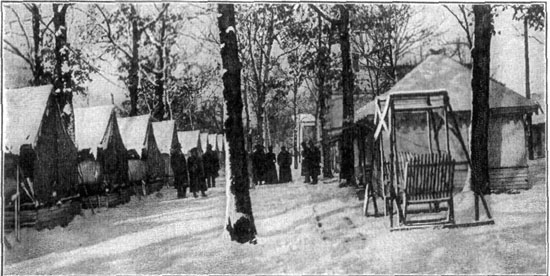

163 A Tuberculosis Tent Colony in Winter

165 An Outdoor Classroom for Tuberculous Children